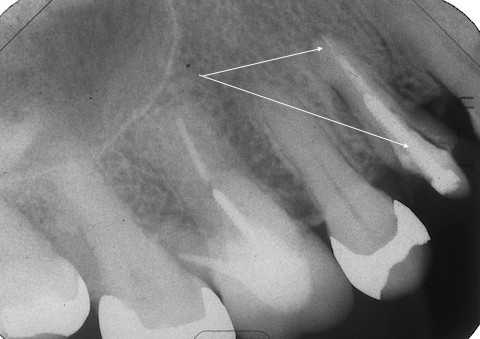

70代女性、右上4、歯根破折前回のつづきこの歯は1年ほど前に前医で治療を受けた時に、割れているので近いうちに抜歯になると言われたそうだ。そこはインプラントをしている歯医者だったので、インプラントは勧められなかったの?とお訊きしたら、そんなことは抜く直前しか言われないそうだw1週間後、とりあえず抜いてみた。かなり歯質は薄くなっていたので、抜くのも難しい。抜歯鉗子で握り潰してしまいそうだ。抜いて見てみると、完全離断ではなかったが、クラックがあるかもしれなかったので、抉り割ってみた。あとは綺麗にして、スクリューポストを入れて再建していくのだが、根尖口とは違うところにリーマーが飛び出して折れていた。また、根管充填材はFeS(硫化鉄)で黒くなっていた。これは硫酸塩還元細菌が生息していたということを意味しており、根管内は細菌で汚染されていたということだ。緊密な根管充填は垂直加圧法以外では見たことがない。所詮、人間のすることなどこの程度だ。これでは遅かれ早かれ歯はだめになってしまう。神経を取るなど最初からしないのが一番良いのだが、抗生剤も普及しているにもかかわらず。なぜこんなことを100年以上もし続けるのだろうか? 歯科医師は歯学部を卒業するまでに完全に洗脳されてしまうようだ。今日は抜歯するまで、まずはレントゲン写真でのbefore/afterだ。beforeリーマーが折れこんでいるのが見えると思う。after抜歯はかなり手こずった。壊しそう。。抜歯窩は膿瘍を丁寧に搔爬し、洗浄しておくつづく